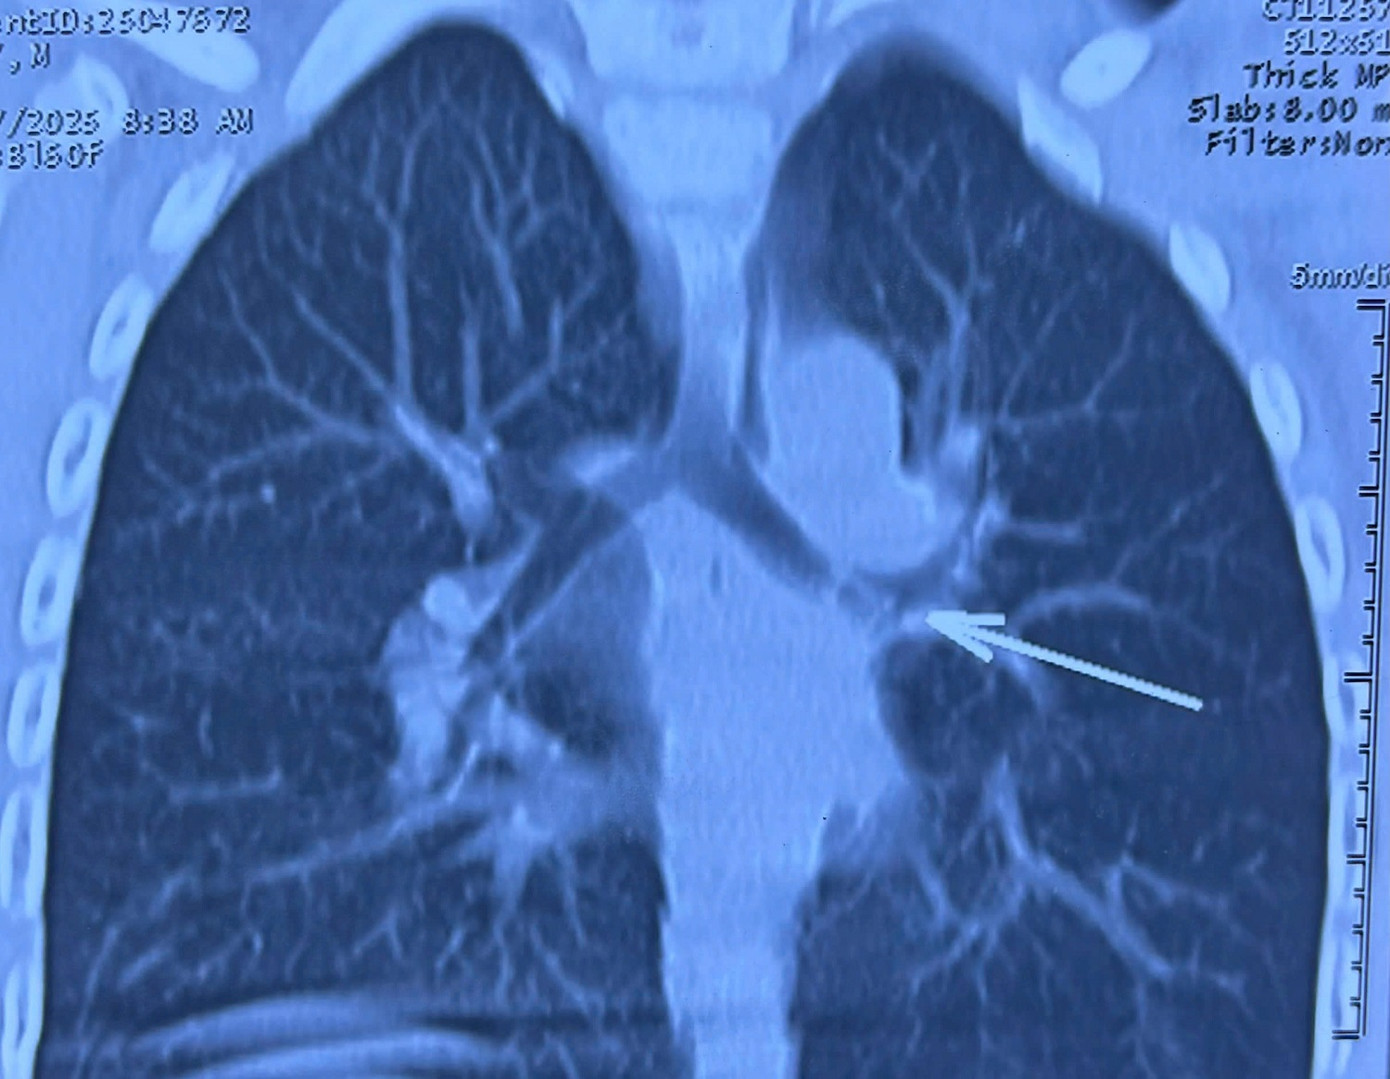

| Dị vật nằm trong đường thở của bệnh nhi được phát hiện qua hình ảnh kiểm tra |

Tại Bệnh viện Tai Mũi Họng TP.HCM, các bác sĩ nghi ngờ dị vật đường thở và nhanh chóng chỉ định chụp CT-scan ngực. Hình ảnh cho thấy dị vật dài khoảng 10mm nằm ở phế quản gốc trái. Ê-kíp trực do BS-CKII Nguyễn Thanh Tùng- Khoa Mũi Xoang, đã tiến hành nội soi phế quản ống cứng và gắp ra một chiếc kèn nhựa nhỏ – chính là thủ phạm phát ra tiếng “kèn” mỗi khi bệnh nhi thở.